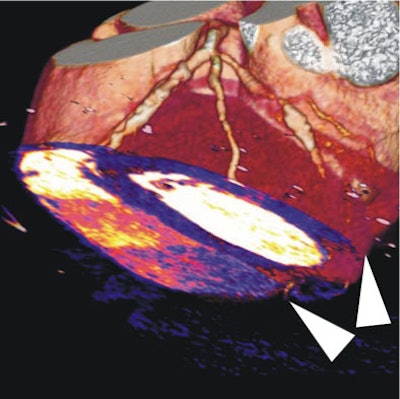

| In a 64-year-old man with chest pain, image of the corresponding slice shows inferior ischemia (arrows). |

In all territories where dual-source CTA showed blood-pool deficits, SPECT or catheter angiography confirmed ischemia or critical stenosis, they concluded.